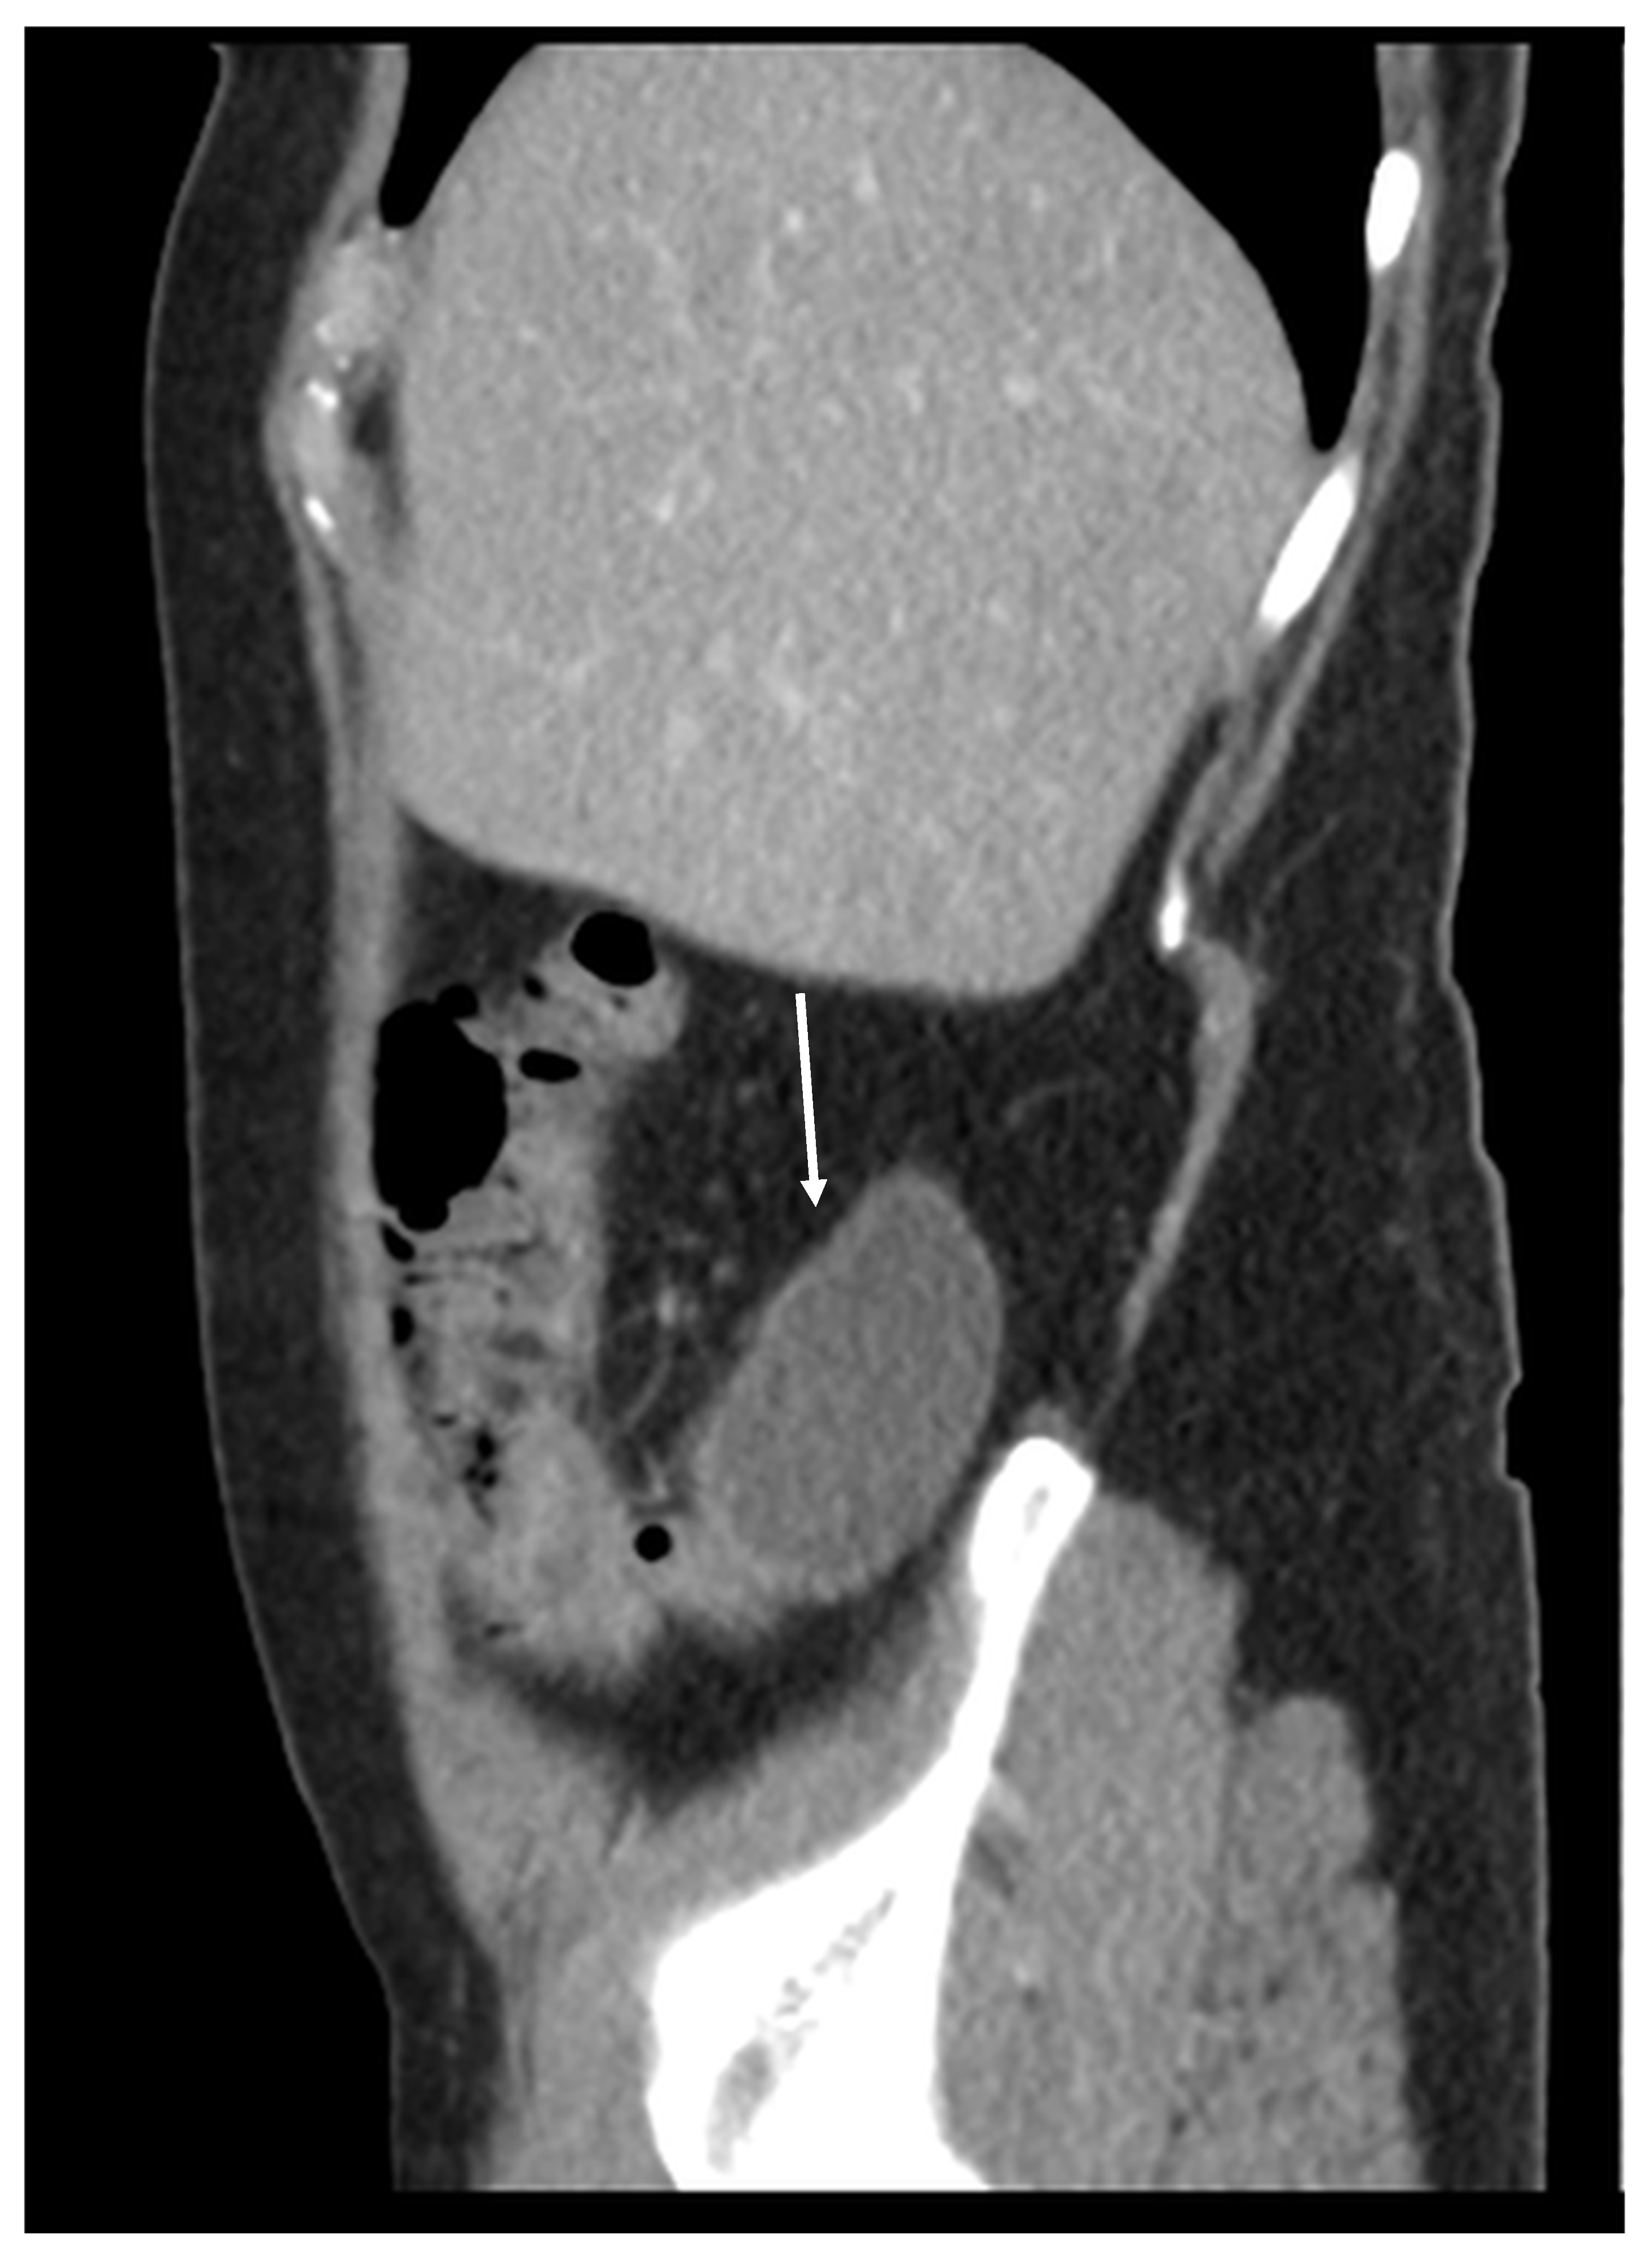

Patients with a misdiagnosed rupture of the mucocele may develop pseudomyxoma peritonei. It is characterized by the presence of an abundant gelatinous substance in the abdomen. Diffuse, progressive, and abundant mucin-containing tumor cells are typical of this disease [2] (Figure 11, Figure 12, Figure 13, Figure 14, Figure 15 and Figure 16). The interval between rupture and advanced disease is several years. In our clinical series, the interval was about 5 years. In the literature, we found a wide range of this interval from 12 months to 10 years [9,10]. The natural history of PMP revolves around the “redistribution phenomenon”, whereby mucinous tumor cells accumulate in the Douglas pouch, in the diaphragm (more on the right), and the small and large omentum (Figure 17). The small intestine is less involved [4]. Pseudomyxoma peritonei is a slowly progressing disease, which fills the peritoneal cavity over time. There are several classifications of pseudomyxoma. The most commonly used is the PSOGI classification [2]. Mucinous accumulation progresses to malnutrition, bowel obstruction, and respiratory compromise. Rarely, the tumor may spread to the pleural cavity. This has been described in 5.4% of cases. It may occur spontaneously or as a result of diaphragmatic injury during cytoreduction [8,11].

Figure 11, Figure 12, Figure 13, Figure 14 and Figure 15. Advanced stage of the disease. The abdomen is full of tumors and mucin. Typical signs are heterogeneous or hypodense masses in the form of lobules often with septa, which could be enhanced by contrast and could be associated with calcifications.

Figure 15. CT, venous phase, sagittal plane.